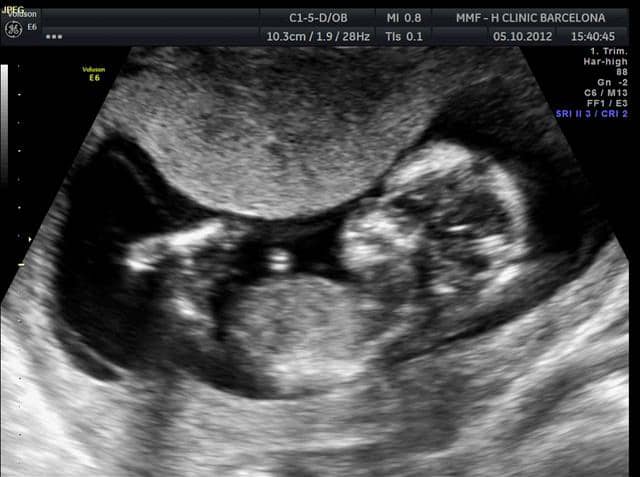

Por una parte se encuentran ya mucho mejor de algunos síntomas muy molestos especialmente nauseas pero también otros como cansancio o facilidad para los mareos. La cara va adquiriendo sus rasgos y se parece cada vez a la de un bebé. En este momento del embarazo los párpados del bebé se han fusionado para proteger los ojos a medida que se forman.

Pero en la segunda mitad del embarazo el necesitarás ganar un poco más de una libra por semana. El feto mide entre 70 y 80 mm y pesa de 13 a 20 gramos. Estando en la semana 13 de embarazo me sentí súper bien.

En esta semana el feto sigue desarrollándose de forma rápida y constante destaca el aumento de peso y tamaño del embrión. Si tienes 13 semanas de embarazo con gemelos. Semana 13 de embarazo.

A partir de las 13 semanas de embarazo tu bebé crecerá y aumentara de peso de forma rápida su cuerpo aumenta más rápido de tamaño que su cabeza. 13 semanas de embarazo. Semana 13 de embarazo.